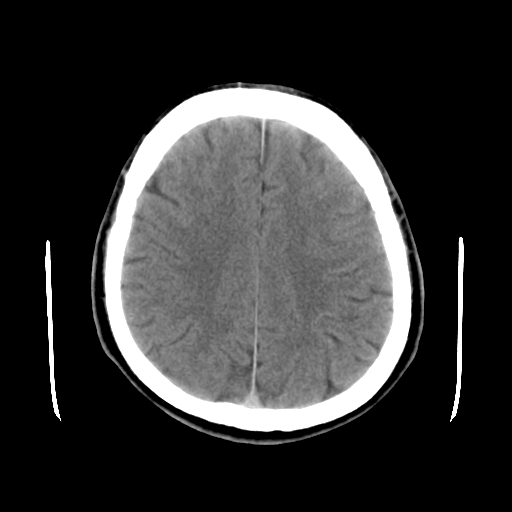

标题: CT15194:男,53岁,头痛、恶心三天。 [打印本页]

男,53岁,头痛、恶心三天。

筛窦囊肿、颅内未见明确异常